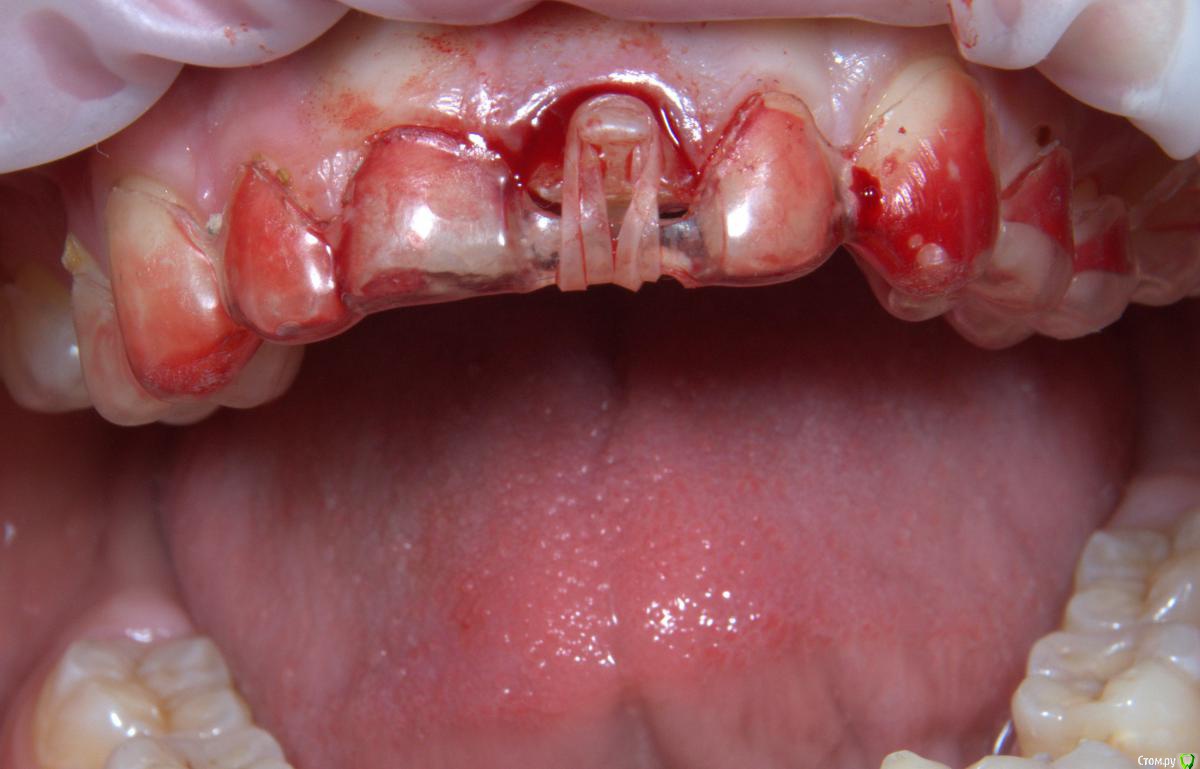

Art 7 Опубликовано 11 августа, 2017 Поделиться Опубликовано 11 августа, 2017 ставишь стекловолоконную балку между апроксимальных поверхностях соседних зубов) Ссылка на комментарий

kamranchick Опубликовано 11 августа, 2017 Автор Поделиться Опубликовано 11 августа, 2017 ставишь стекловолоконную балку между апроксимальных поверхностях соседних зубов)Спасибо Артурчик)Попробуем так))) просто шатается сильно, страшно трогать пока что) Ссылка на комментарий

1586Doc Опубликовано 11 августа, 2017 Поделиться Опубликовано 11 августа, 2017 (изменено) Это обычная силиконовая каппа ?вытягиваем, потом стабилизация ? Как на долго? Изменено 11 августа, 2017 пользователем 1586Doc Ссылка на комментарий

kamranchick Опубликовано 11 августа, 2017 Автор Поделиться Опубликовано 11 августа, 2017 Это обычная силиконовая каппа ?вытягиваем, потом стабилизация ? Как на долго?капу сделали вакуум формером, помоему она пластмассовая вроде. стабилизация 2-3 месяца... Ссылка на комментарий